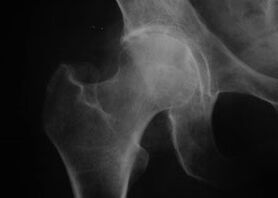

Coxatrosis, artrosis de la articulación de la cadera.

En esta enfermedad se observa un cuadro clínico clásico de artrosis.

El primer síntoma de la coxartrosis es el malestar en la articulación de la cadera después de la actividad física.

Con la coxartrosis progresiva, aumenta el dolor, aparecen rigidez y dificultad de movilidad.

Los pacientes con coxartrosis grave respetan la extremidad afectada, evitando pisarla y, estando de pie, eligiendo posiciones en las que se sienta menos dolor.